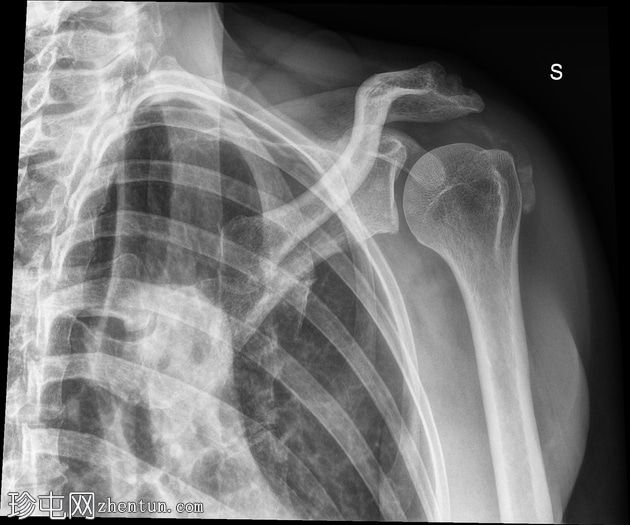

轴位

可见肱骨头周围、三角肌腱和冈上肌腱之间有钙化沉积物,呈致密均匀的阴影。